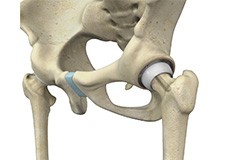

Hip Resurfacing

The hip joint is also known as a ball and socket joint, where the ball (femoral head) of the thigh bone fits into the socket (acetabulum) of the pelvic bone.